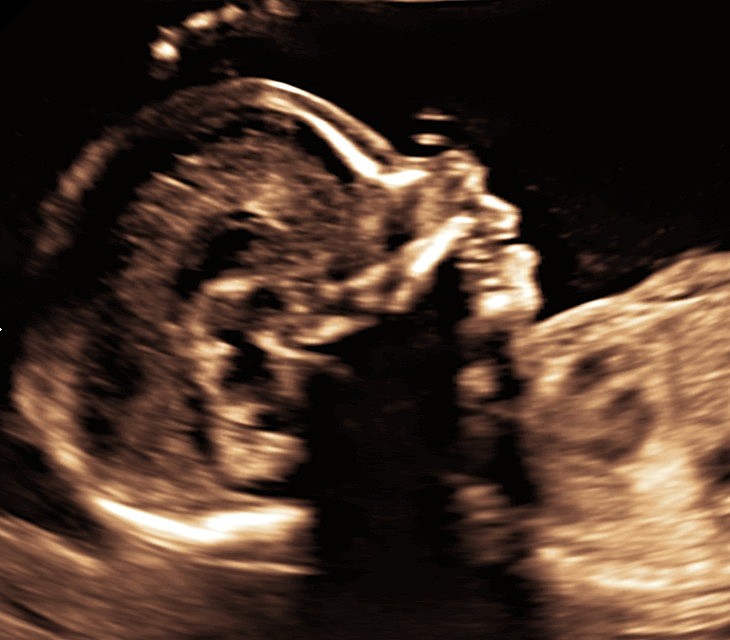

Anomaly Scan

Detailed fetal anatomy, placental assessment and Doppler screening—delivered within a consultant-led care pathway

The 20-week anomaly scan is a key milestone in pregnancy and the next major assessment after the nuchal scan. At this stage, your baby’s organs and structures are sufficiently developed to allow a detailed evaluation of growth and anatomy, helping to identify or rule out major structural conditions.